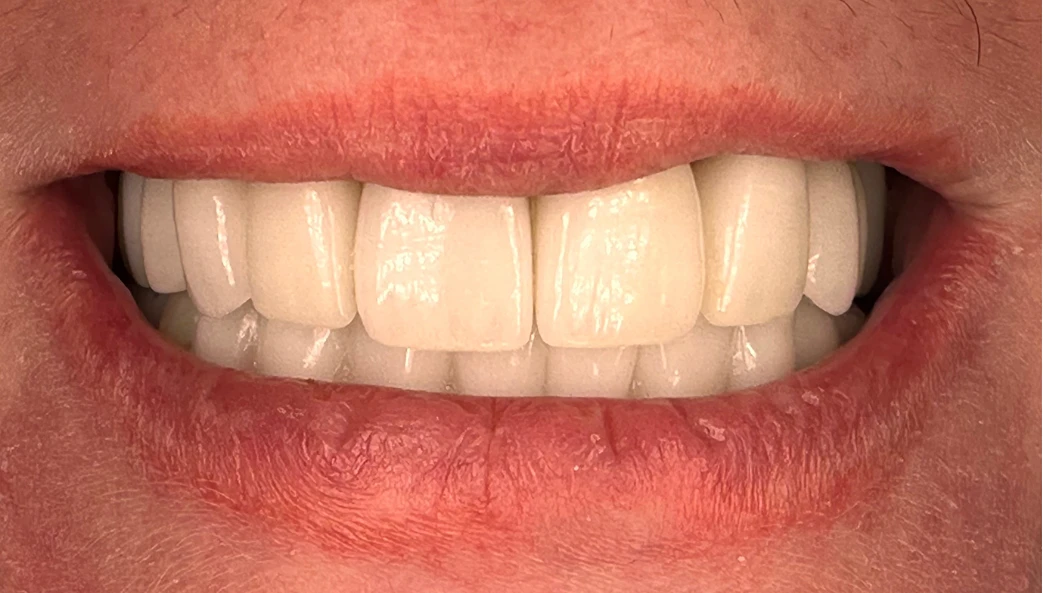

Final Result

The transformation speaks for itself.

Her final shade choice?

A bold bleach white, reflecting the new chapter she envisioned — and it looks stunning.

Today, she attends regular hygiene visits, proudly shares vacation photos from Disneyland and Europe, and tells us how she smiles freely for the first time in years. Her words:

"I feel like a new person. I can finally smile without hiding."